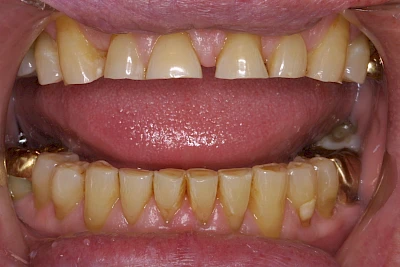

- Abnutzung durch Kauen (Abrasion) oder duch durch übermäßiges Knirschen bzw. Pressen (Attrition)

- Knirschen bzw. Pressen und ungünstige Putztechnik (Druck): keilförmige Defekte

Eine Sonderform sind sogenannte keilförmige Defekte im Bereich der Zahnhälse. Hier geht man davon aus, dass Knirschen und Pressen in Kombination mit falschen Putzgewohnheiten (zu hoher Putzdruck, Verwendung von Zahnpasta mit hohen Abrasionswerten) eine Rolle spielen.